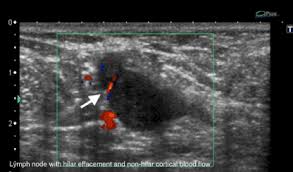

Did not respond to antibiotic and was referred for biopsy. Inflammatory breast cancer develops when cancer cells block lymph vessels. We'll show you breast cancer pictures to help you identify any physical traits of the condition. The aim of this study was to evaluate the features of inflammatory breast carcinoma (ibc) on mri compared with mammography and ultrasound and to better define the role of mri in patients with this aggressive disease. Online says it develops suddenly.

It's called inflammatory because that's how it looks. Any area that does not look like normal tissue is a possible cause for concern. Inflammatory breast cancer, also known as carcinomatous mastitis, t4d, or pev 2 or 3, is the only real therapeutic emergency in breast oncology, given the high risk of metastasis, the reason for the most unfavourable prognosis of all breast cancers.it must consequently be diagnosed rapidly, and imaging examinations must in no case delay therapeutic management. Because ibc grows quickly, it is usually found at a locally advanced stage, meaning that cancer cells have spread into nearby breast tissue or lymph nodes. A breast ultrasound is a scan that uses penetrating sound waves that do not affect or damage the tissue and cannot be heard by humans. Ultrasound is useful for looking at some breast changes, such as lumps (especially those that can be felt but not seen on a mammogram) or changes in women with dense breast tissue. As these inflammatory breast cancer picture shows, the texture of the breast may change and appear to look dimpled or ridged, like an orange peel. Their differences, however, lie in their enhancement.

Most inflammatory breast cancers are invasive ductal carcinomas, which means.

However, inflammatory breast cancers are more likely to show solid mass lesions. The problem is that inflammatory breast cancer can look very much like mastitis early on, and is often diagnosed only after a woman has been treated first for mastitis (often with no improvement in symptoms). This condition usually does not develop a lump, but commonly affects the breast skin. The aim of this study was to evaluate the features of inflammatory breast carcinoma (ibc) on mri compared with mammography and ultrasound and to better define the role of mri in patients with this aggressive disease. These tubes, which are hollow, allow lymph fluid to drain out of the breast.